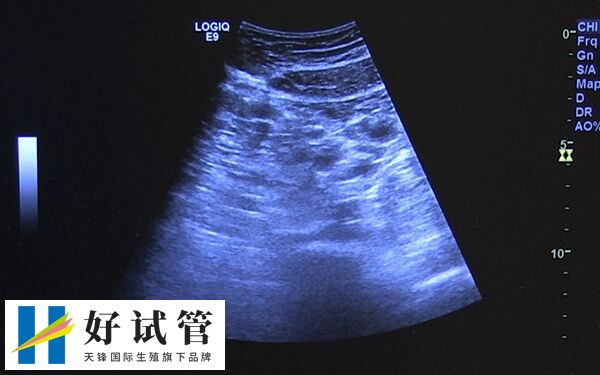

长方案促排卵泡大小不一怎么回事

在试管长方案促排过程中,若是有出现卵泡大小不一的情况,可能是女性内分泌出现异常,导致部分卵泡发育较快,而其他卵泡发育较慢。同时也可能是卵泡对药物的反应各不相同导致出现的大小不一,或是卵巢功能减退等,对于这种情况,建议患者应及时前往医院寻求帮助。

试管临床上,长方案促排卵泡治疗周期应用的比较多,不过因个体之间存在较大的差异,所以部分患者在使用长方案促排卵之后,可能会出现卵泡大小不一样的情况,而这也可能是以下几点导致的。